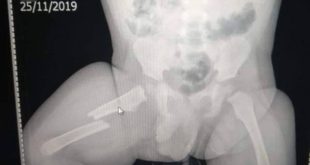

Osso da criança foi quebrado após discussão na casa de sua família Foto: Divulgação/Polícia Civil RIO — Um homem foi preso pelo crime de tortura após, segundo a Polícia Civil, ter fraturado o fêmur do próprio filho de 11 meses, em Nova Iguaçu, na Baixada Fluminense. Identificado como Claudinei Lourenço Costa da Silva, de 18 ...